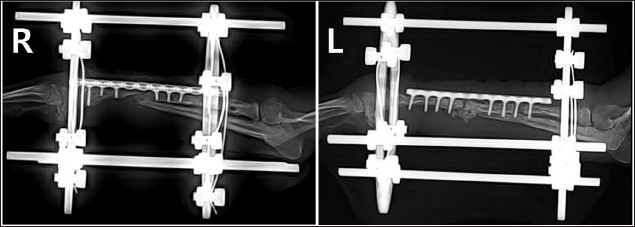

A two-step surgical plan was developed for managing the fractures. The remaining pin was removed in the first surgery and a CEF was applied for temporary fixation (Fig. 2A and B). Pins used included two 0.9 mm K-wires placed proximally and distally in a crossed manner, and one 1.2 mm olive wire placed in a single location. Anticipation of bone regeneration around areas of bone lysis near screw holes, and physical rehabilitation focused on inducing forelimb use until the second surgery. During the 6-week maintenance period of the temporary external fixation device, partial bone regeneration was observed in some areas of bone loss (Fig. 2C and D). Although forelimb ambulation remained plantigrade, there was an improvement in utilizing the limb smoothly with weight-bearing. In the second surgery, the CEF device was removed, and a surgical approach was made to apply the bone plate. The atrophied fracture sites on both sides showed no signs of bone regeneration and were partially debrided to expose the bone marrow cavities. The fracture was then fixed with a long bone plate and 1.5 mm screws. Autografts were harvested from the iliac wing and transplanted around the fracture site. This procedure was performed identically on both limbs with the fascia and skin closed in a standard manner. Additionally, CEF methods involved applying 0.9 mm K-wires, the same size as those used in the first surgery, above and below the plate on the fractured radius to provide further stability (Fig. 3).

Fig. 2. Radiographs taken immediately after the first surgery and 6 weeks postoperatively, showing the effects of temporary circular external fixation on bone remodeling. (A) Immediate postoperative view of right radius and ulna. (B) Immediate postoperative view of left radius and ulna. (C) 6-week postoperative view of right radius and ulna. (D) 6-week postoperative view of left radius and ulna.